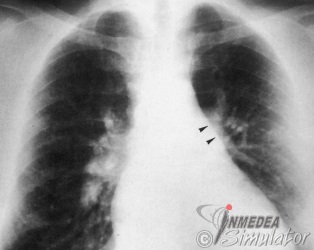

Abbildung 44. Erweiterung des Hauptstammes der A. pulmonalis (Pfeilspitzen). Große, gefäßtypisch konfigurierte Hili. In Anzahl und Kaliber vermehrte Lungengefäße. Apikal und basal gleichmäßige Durchblutungsverteilung.